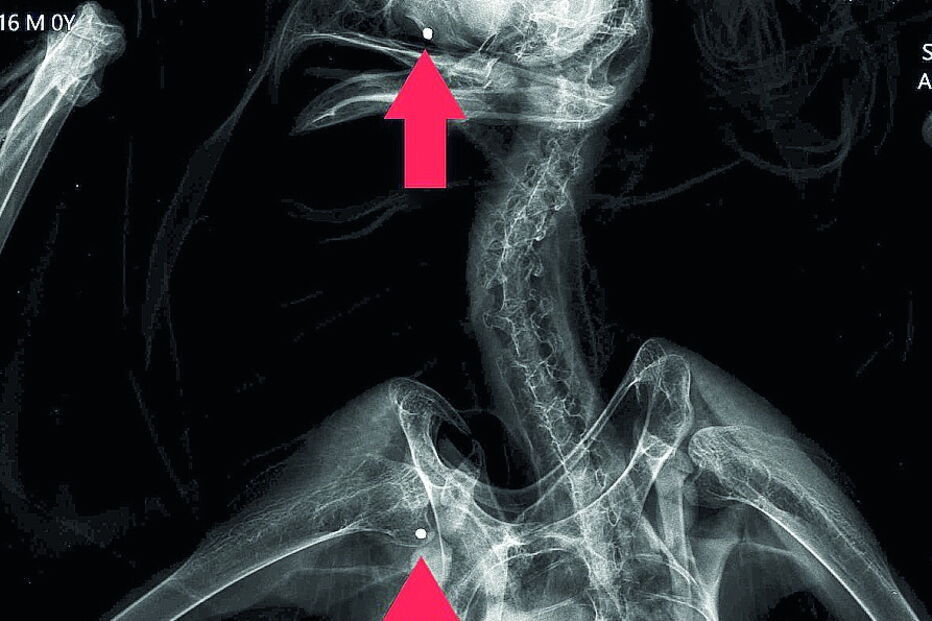

Ave ficou ferida após ser atingida com tiros de caçadeira.

A águia, que tem o estatuto de ‘Quase Ameaçada’ em Portugal, terá sido alvejada também no Alentejo, em meados de agosto. Foi encontrada em Moura e depois levada para o RIAS. No centro, o exame radiológico detetou três projéteis de caçadeira: na cabeça, ombro direito e costado esquerdo. Foram ainda descobertos restos de um quarto projétil.

"Foi possível retirar um dos projéteis, mas os restantes não puderam ser extraídos por questões médicas", explica o RIAS. Foi colocada uma ligadura na asa da águia, que ficou numa câmara de recuperação interior, onde foi mantida sob vigilância constante.